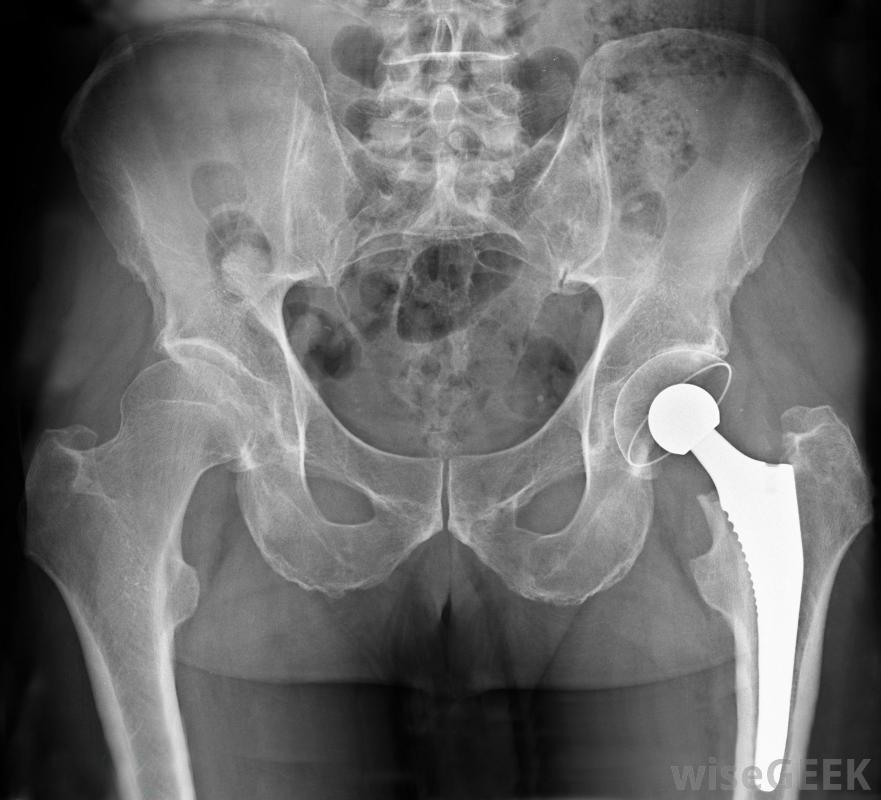

骨科植入物是植入骨骼和關節以恢復正常功能的人工裝置。通常,當髖關節、膝關節、肩關節或肘關節因損傷或骨關節炎等疾病而受損時,骨科植入物起到關節置換的作用,關節磨損會導致疼痛和僵硬植入物通常只在非手術治療方法失敗的情況下使用。植入物往往會在數年后磨損,因此,給年輕人使用的植入物在某些時候可能需要更換。骨科植入物可以幫助患有骨關節炎的人增加他們的活動性。許多不同的材料被用來制作骨科植入物,包括塑料,陶瓷和金屬,如不銹鋼和鈦。植入物可以通過多種方式固定到位。可以使用水泥或螺釘固定,也可以通過周圍環境的壓力將其固定到位。通常,從矯形植入物周圍生長的骨可以幫助固定。有時,植入物的一部分在另一部分沒有骨水泥的情況下,如髖關節置換術,稱為混合型髖關節,其中承載關節球形部分的柄可以用水泥固定,而接收杯則不是骨盆區域的X光片,顯示一個金屬置換髖關節鈦制骨科植入物具有強度高但重量輕的優點,而且人體通常不會對其產生反應。缺點是,骨細胞很難粘附在金屬的閃亮表面上,因此在愈合過程中很難與骨融合。研究進展正在尋找新的蝕刻方法一種稱為納米管的微型管進入鈦表面,這是一種以前成本太高而不實用的方法。這些納米管的結構使它們對水具有吸引力,并為細胞的生長提供了一個合適的環境雖然骨科植入物有好處,如增加活動性和減少與損傷或退行性關節疾病相關的疼痛,但偶爾也會出現一些缺點。植入物可能會松動或斷裂,身體很少會對其產生反應。有時可能會發生感染,這使得有必要更換植入物。細菌可以在骨科植入物的表面生長,形成所謂的生物膜,要解決這個問題,必須在安裝替代物之前移除植入物并治療感染。對所謂的水凝膠的研究可能會給未來帶來希望,由于這些吸水性物質對細菌不友好,同時仍允許骨細胞生長,因此可以將它們添加到植入物表面,以盡量減少感染的機會。